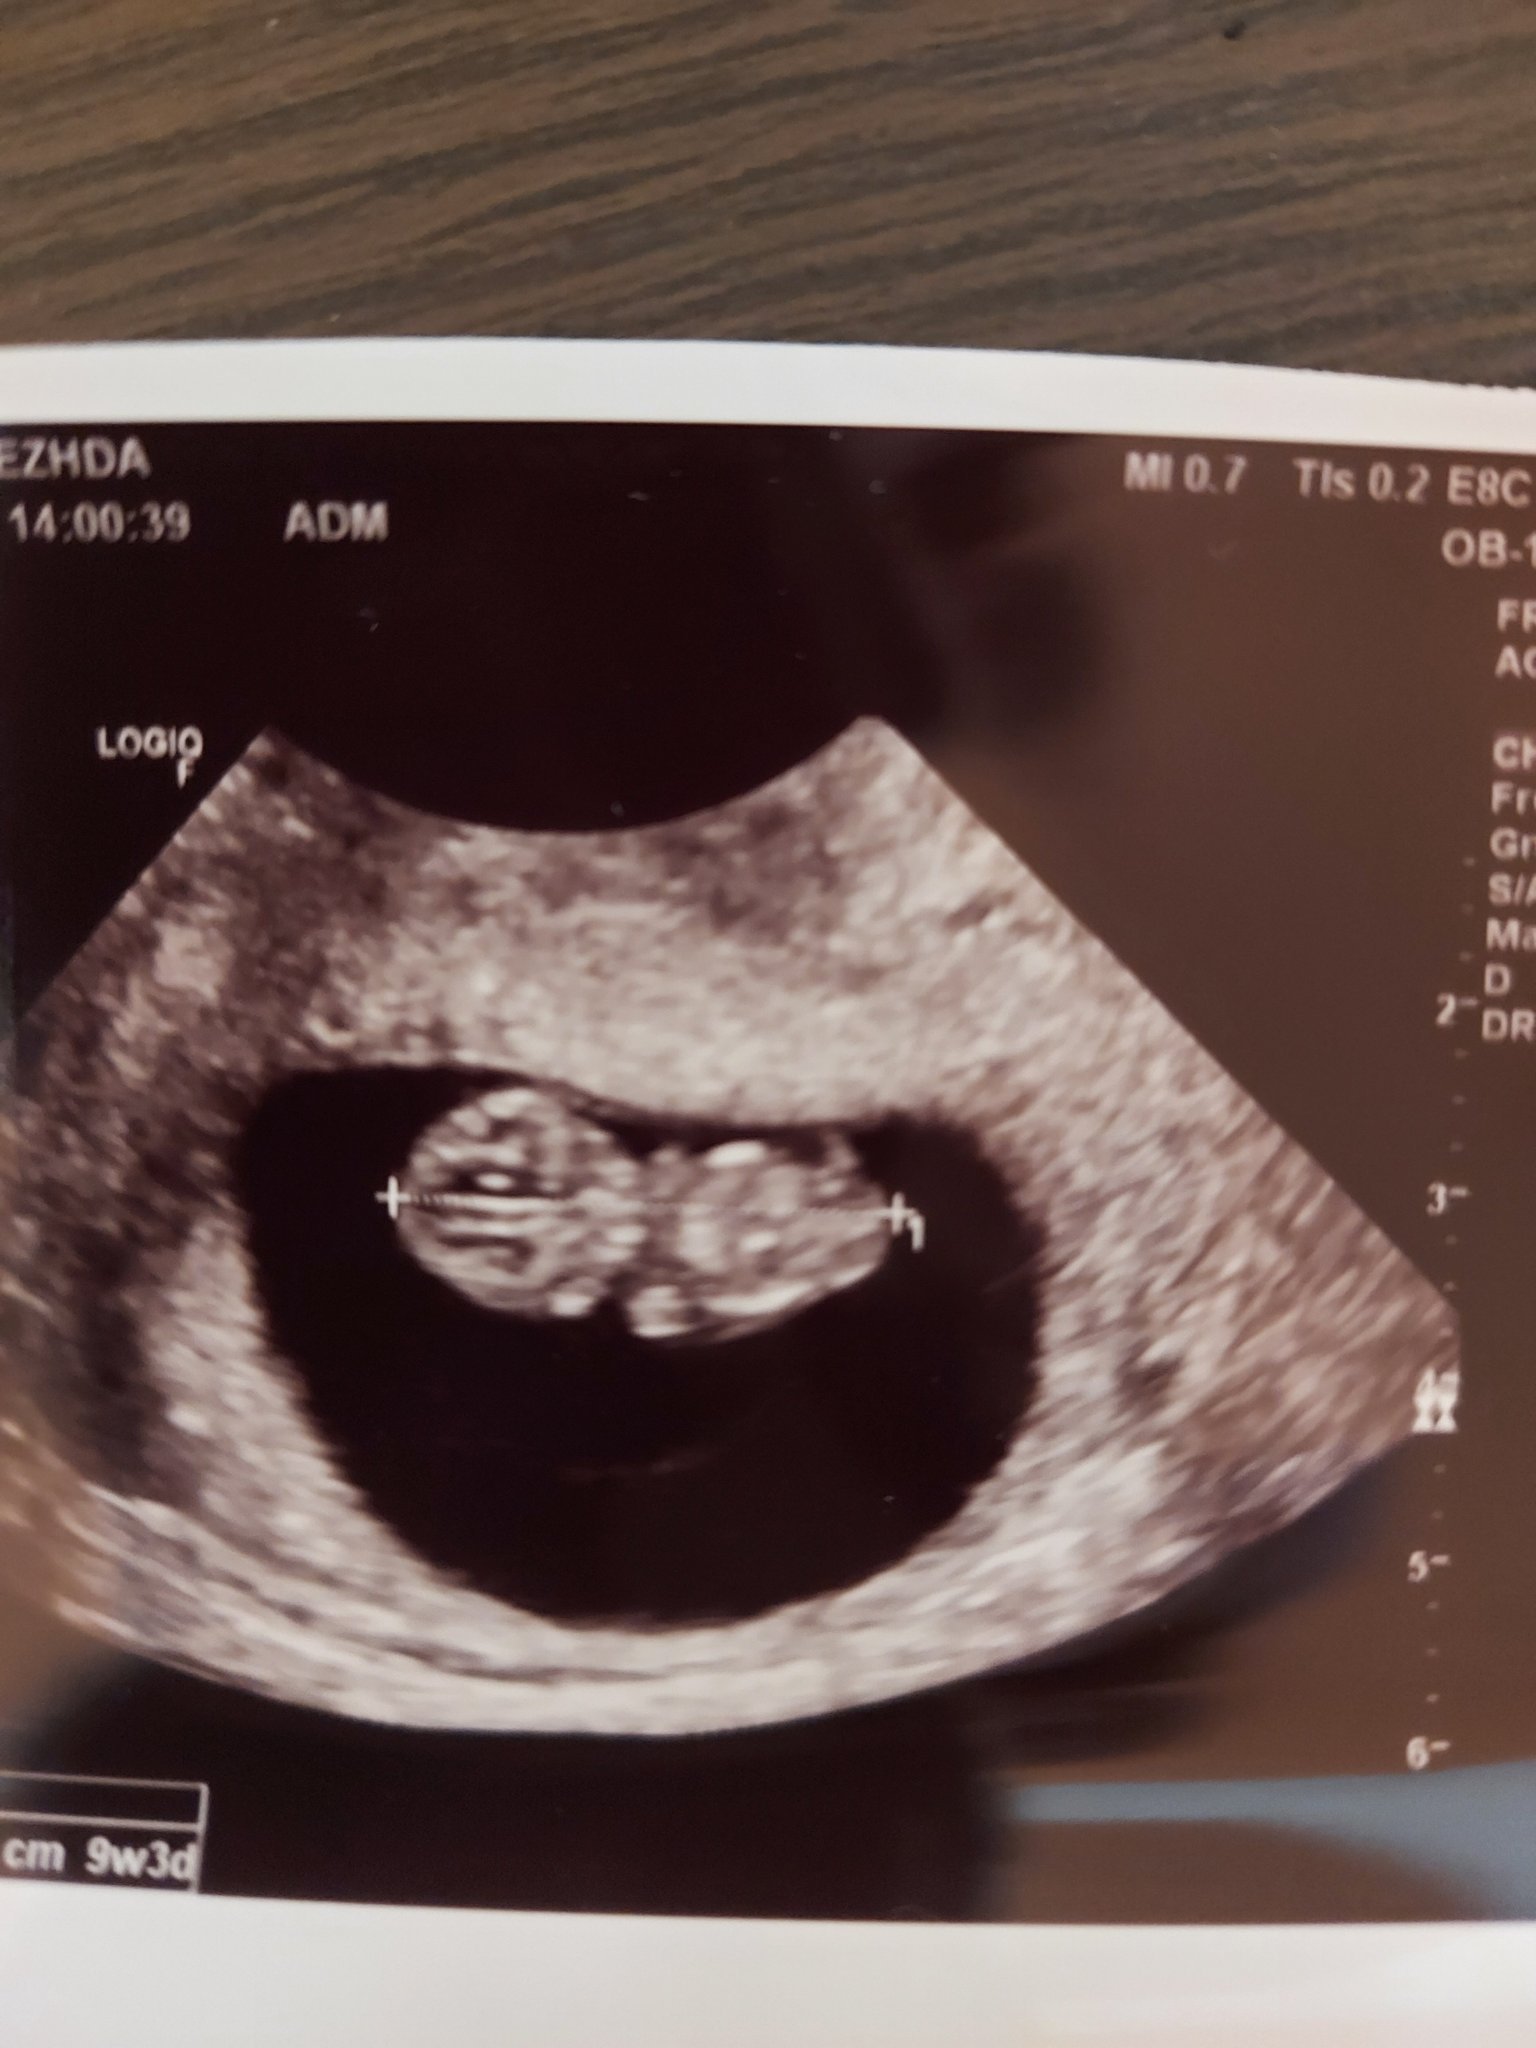

• Мнения: X

Здравейте, момичета. От днес съм в 9 седмица и от обяда имам една гадна тежест в стомаха(не корема) , дискомфорт като къркорене, като все едно е подут... Даже немога да го обясня. Появи се слвд като на обяд повърнах веднъж. Някоя от вас да е имала такива симптоми, че малко сд притеснявам